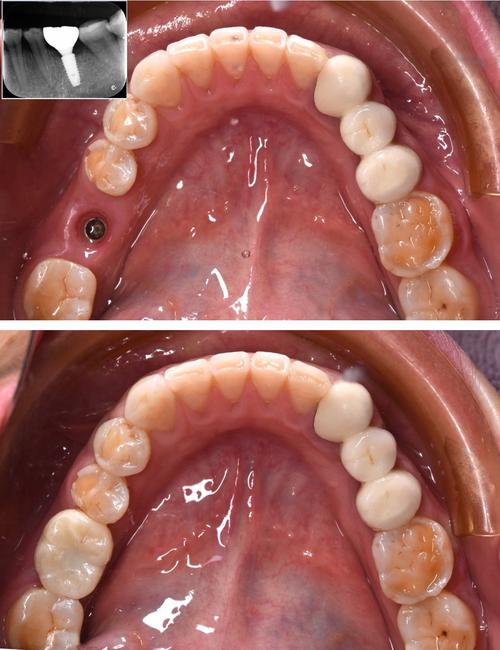

戴牙冠:

(图片来源网络,侵删)- 牙冠制作完成后(通常需要1-2周),医生会将其固定在基台上。

- 调整咬合,确保舒适、功能正常、美观自然。